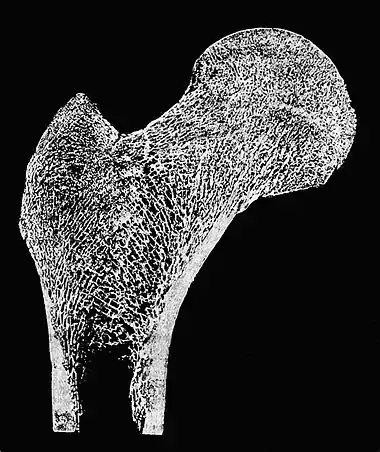

Fig. 5.—Section of Head of Femur, to show the arrangement of the fibers of bone so as to give strength to it. (From Donald Macalister.)